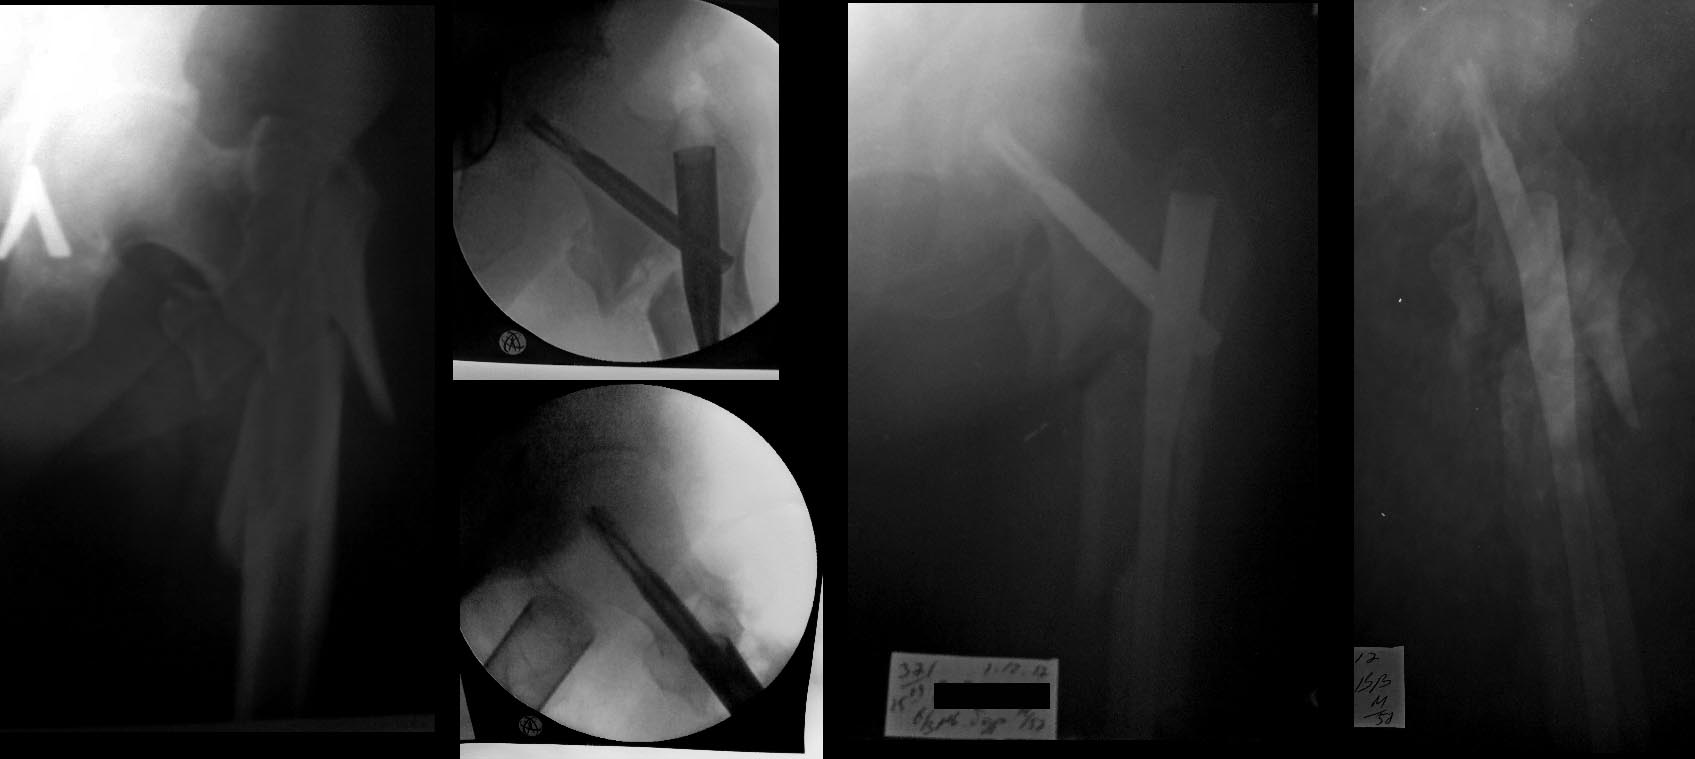

Пациент 57 лет повышенного питания ок.110-115 кг.соматически здоров, оперирован 1.12.17.-закрыто БИОС PFN-a long,

(имплант без возможности первичной компрессии), имеется удлинение конечности на 2,3-3 см.

Какова программама реабилитации и нагруки в данной ситуации уместна? Спасибо за участие.